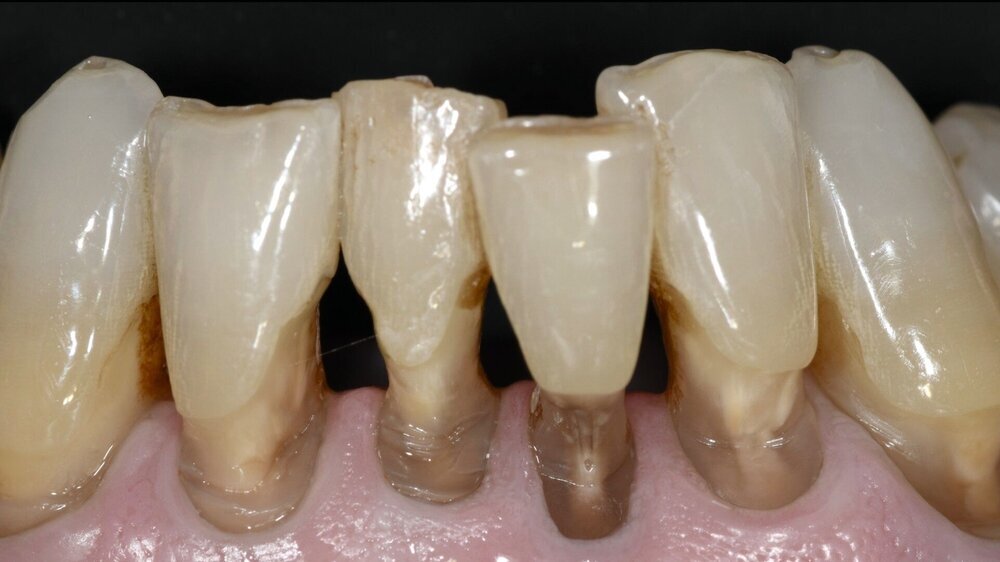

Ein sich seit vielen Jahren bei mir in Behandlung befindlicher 75-jähriger Patient klagte zunehmend über Hypersensibilitäten an den unteren Frontzähnen, die im Zahnhalsbereich ausgeprägte Zahnhartsubstanzdefekte aufwiesen (Abbildungen 1a–1d). Die Mundhygiene wurde als gut eingestuft. Möglicherweise waren die vorliegenden Zahnhalsdefekte als sogenannte Putzdefekte zu klassifizieren, wie sie bei intensiven Mundhygienebemühungen häufig zu beobachten sind.

Mit zunehmendem Alter hatte der Patient allerdings Mühe, die schwer zugänglichen Defekte adäquat zu reinigen. Zudem musste man befürchten, dass es bei weiterem Abbau der Zahnhartsubstanz in diesen Bereichen zu einem Verlust der Zahnintegrität oder einer Pulpaexposition kommt. Daher wurde entschieden, die besonders stark betroffenen Zähne 31, 32, 41 und 42 mit Kompositrestaurationen im Zahnhalsbereich zu versorgen.